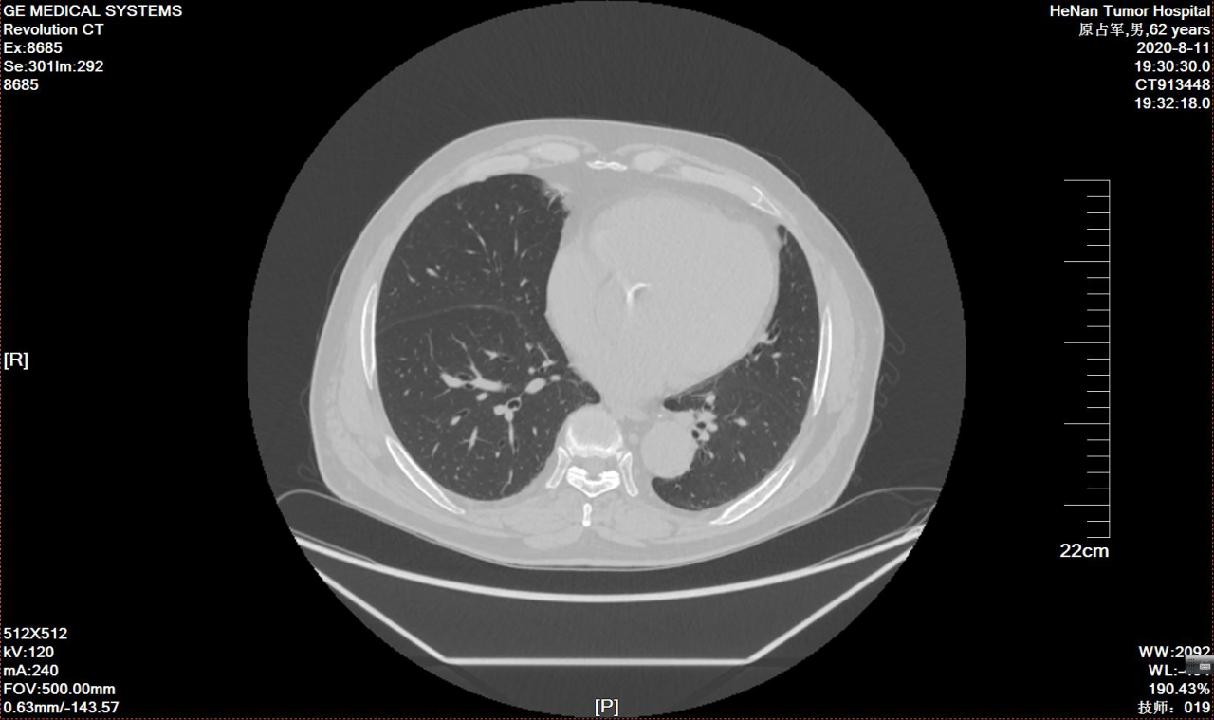

二、下一步?评估病变范围

- 电子计算机断层成像(CT)